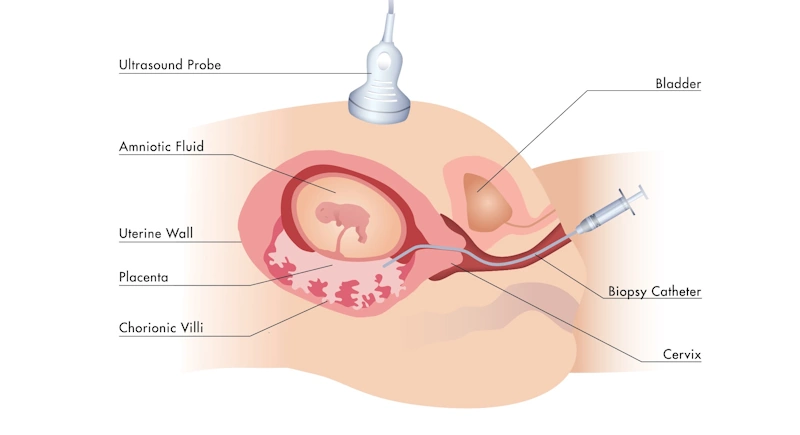

الفحوصات التشخيصية الإضافية

إذا كانت نتائج الفحص الأولي غير مطمئنة، فقد تُوصي الطبيبة بإجراء فحص الزغابات المشيمية (CVS) أو فحص السائل الأمنيوسي (Amniocentesis) للحصول على نتائج دقيقة ونهائية.